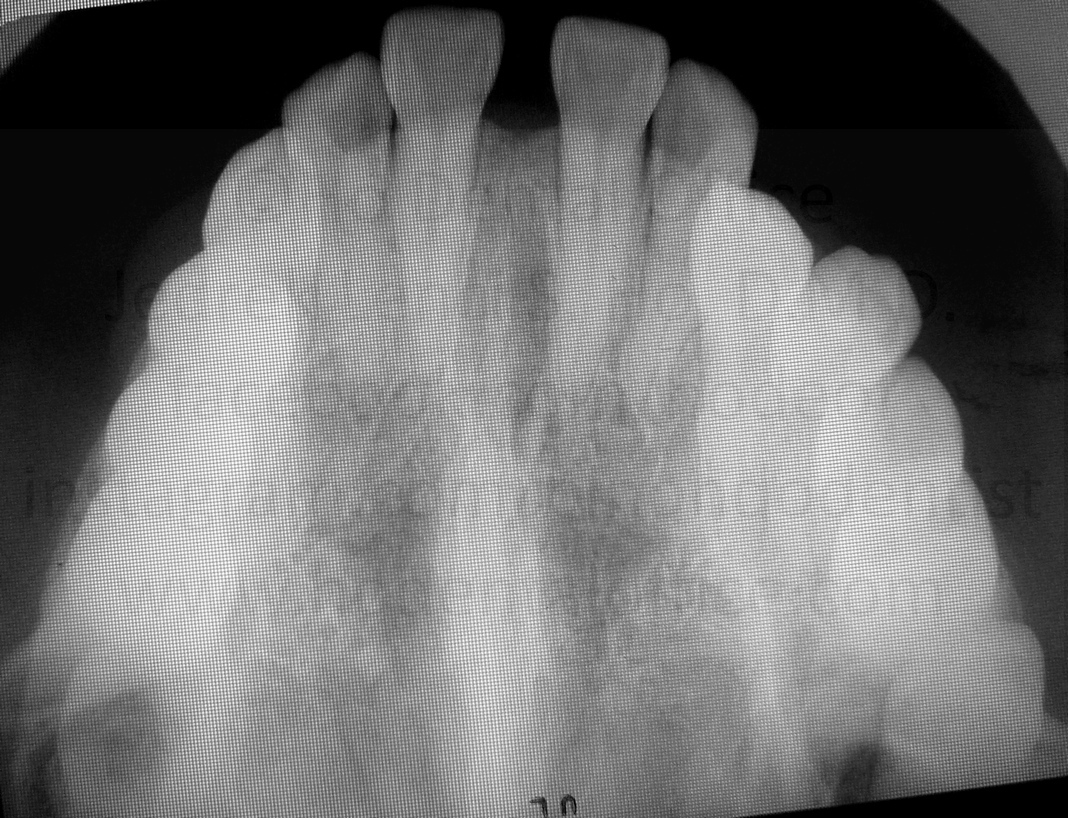

Diastema was successfully closed a year later.

Patient eventually graduated from orthodontic treatment, and came in regularly for cleaning and checkups.

Due to patient's lack of compliance on wearing retainers, minor relapse was observed on the central incisors as of Nov 2025. Measurement was also done to check the height of frenum attachment, which was now a bit higher at 11mm.